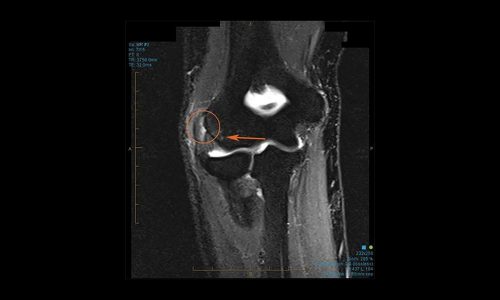

Η έξω επικονδυλίτιδα χαρακτηρίζεται από πόνο ή κάψιμο στην έξω επιφάνεια του αγκώνα και μειωμένη δύναμη δραγμού (πιασίματος). Η διάγνωση γίνεται συνήθως μόνο με τον κλινικό έλεγχο, με δοκιμασίες φόρτισης των εκτεινόντων, όπως έκταση του καρπού υπό αντίσταση ή μέγιστη κάμψη του καρπού. Σε αμφίβολες περιπτώσεις ο νευρολογικός έλεγχος δύναται να αποκλείσει το σύνδρομο παγίδευσης του κερκιδικού νεύρου, το οποίο συχνά μιμείται την έξω επικονδυλίτιδα. Η μαγνητική τομογραφία δεν είναι απαραίτητη, αλλά δείχνει αυξημένο σήμα στην περιοχή έκφυσης των τενόντων.